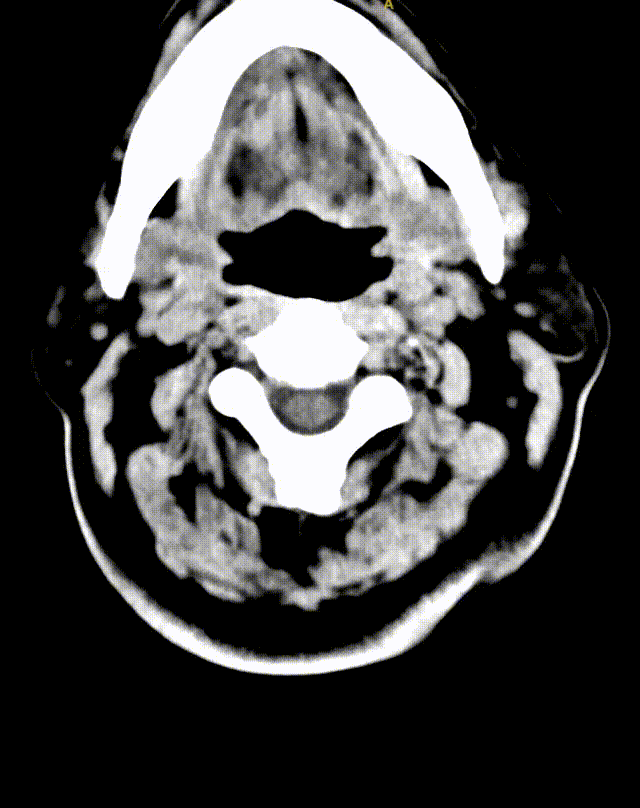

03 术前影像信息

急诊颅脑CT平扫未见异常,必要时MRI检查。

猪尾巴导管行全脑血管造影,可见双侧椎动脉V4段闭塞。

左侧椎动脉造影提示左侧椎动脉V4段闭塞;右侧锁骨下动脉造影提示右侧椎动脉纤细并V4段闭塞。

术后复查CT:双侧大脑及小脑半球稍肿胀。

术后MRI:脑干新发梗死。